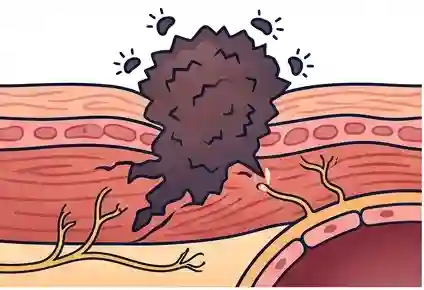

Radiation therapy is a cornerstone of cancer treatment but it carries a long-term consequence that is insufficiently recognised, even within oncology: radiation-induced fibrosis.

Think of healthy tissue as a well-organised fabric flexible, strong, with each thread in its proper place. Radiation damages the connective tissue framework of this fabric. In response, the body lays down scar tissue fibrous, inelastic, and poorly vascularised. Over weeks, months, and sometimes years after radiation therapy, this fibrotic tissue contracts, tightens, and critically entangles and entraps the nerves, blood vessels, lymphatics, and muscles running through the treated area.

The result is radiation fibrosis syndrome a progressive, often painful and debilitating condition that can emerge long after the cancer itself is under control. Many patients and clinicians mistakenly attribute this pain to cancer recurrence, causing additional anxiety and unnecessary investigation.

Radiation fibrosis pain typically develops months to years after treatment ends, long after the patient has been discharged from active oncology follow-up. Many patients with post-radiation neuropathic pain are told “there is nothing more to be done” — yet targeted interventions including nerve blocks, physiotherapy, hyperbaric oxygen, and neuromodulation can significantly improve function and reduce pain. Early referral to a pain specialist is essential.